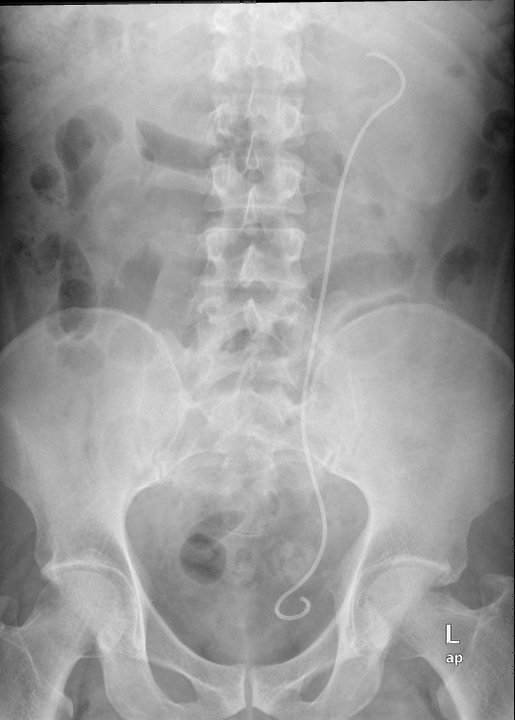

After surgery, there was another KUB done to confirm the location of the stent. The stent protects the ureter from any leftover debris of the pulverised stones.

The X-ray report confirmed that the stent was in the right place. I was out of the OT by 3 pm. At 6pm, the surgeon allowed me to remove the CBD (continuous bladder drainage). I was no longer bed-ridden therefore I was a happy man, and I immediately went down to surau to pray asar and qada’ zohor. Sadly the shops were closed already by then, so I couldn’t buy anything to eat. After 24 hours of observation, I was discharged on Friday morning.